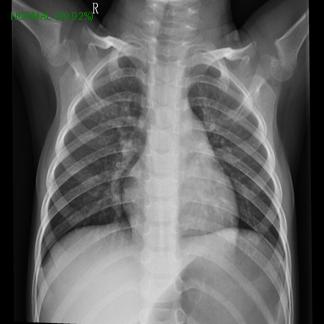

This project uses the DenseNet121 model to detect pneumonia in chest X-ray images. The model is trained on a dataset with train, validation, and test splits from kaggle and demonstrates the use of transfer learning and data augmentation in PyTorch.

Each folder contains JPEG images of chest X-rays.